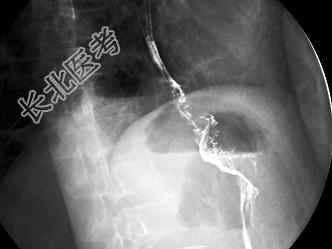

- 单项选择题男,50岁, 进食梗阻1年,结合图像, 最可能的诊断为 ( )

A、食管下段癌

B、贲门癌

C、食管静脉曲张

D、贲门失弛缓

E、胃底癌